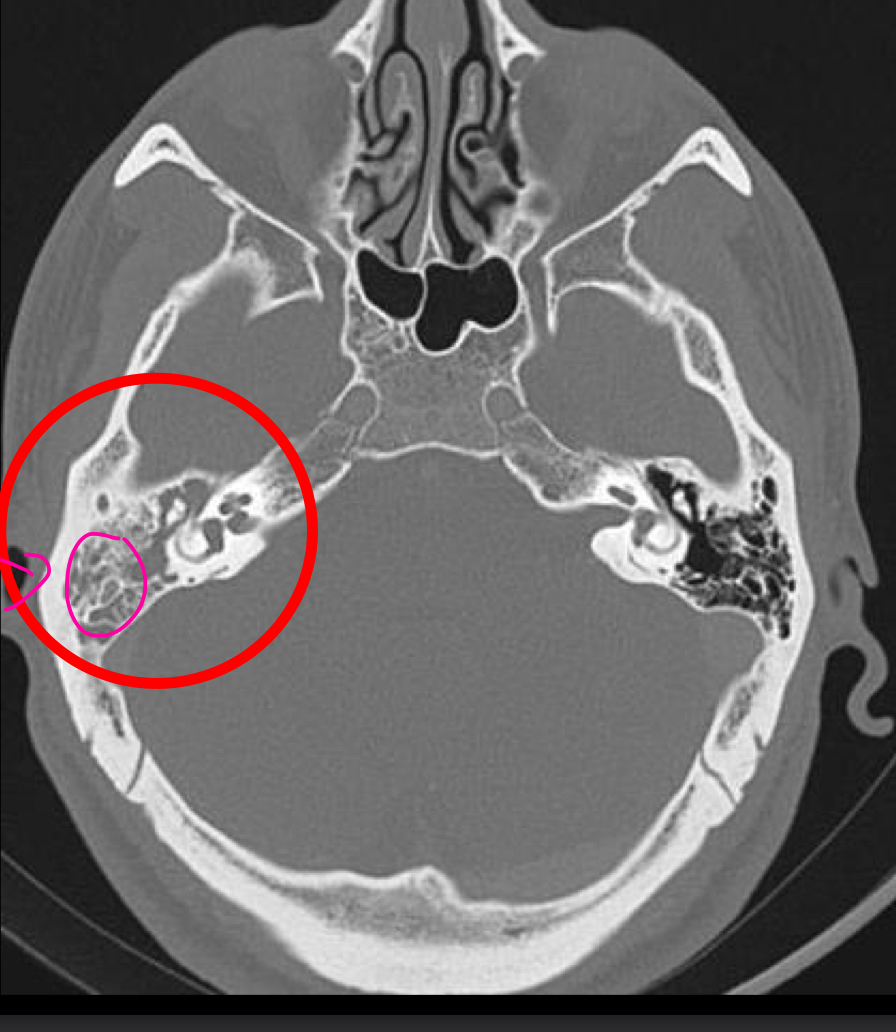

Tc de mastoiditis LO MEJOR

opacificacion de las celdillas mastoideas

coleccion de liquido

cronico= enfrosamiento oseo